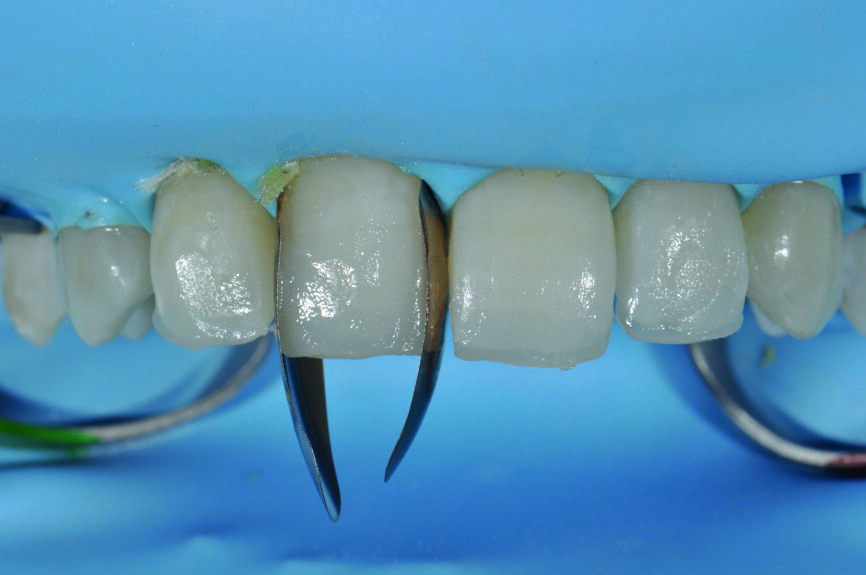

Fig. 4 : a) Gros plan du sourire avant le traitement.

Fig 4b) : vue intraorale latérale.

Fig 4c) : vue intraorale de face.